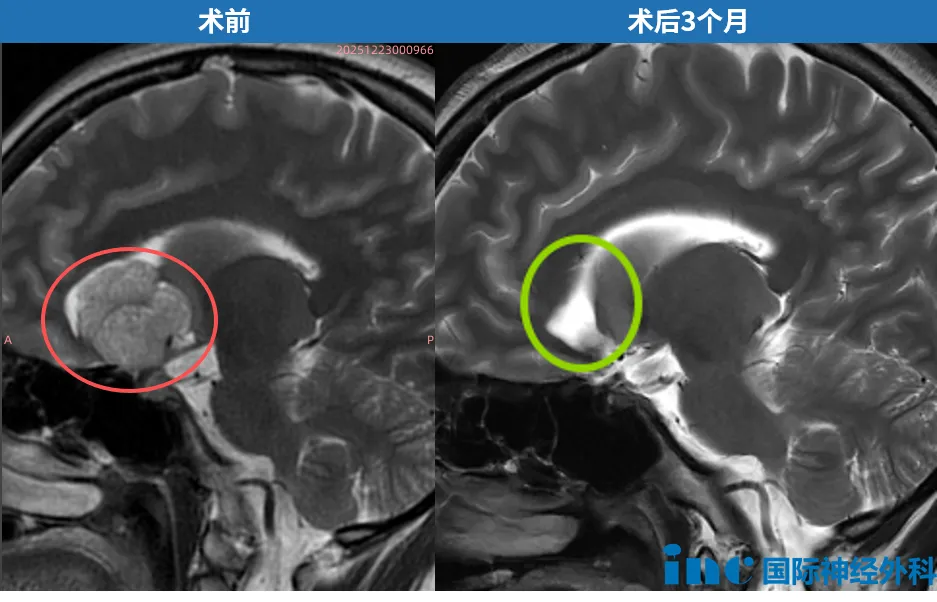

27岁的武女士,是巴特朗菲教授此前的示范手术患者。2025年平安夜,她在巴特朗菲教授主刀下顺利完成手术,垂体瘤全切,垂体柄完整保留。术后不足24小时,武女士平安转出ICU;术后第1天查房,视野与视力均无新发损伤;术后第4天,复查核磁共振证实肿瘤全切。术后3个月,得知巴特朗菲教授再度访华,武女士专程赶赴——既为当面致谢,也为接受系统性术后随访,以影像数据客观评估远期预后。

最新检查结果显示:肿瘤全切,无残留病灶,激素水平维持稳定,远期预后指标良好。除了对巴教授满心的感谢,武女士更希望将这段真实的诊疗历程如实分享出去,为同样面临类似病情的患者,添一份前行的底气。后续报道将详细记录……